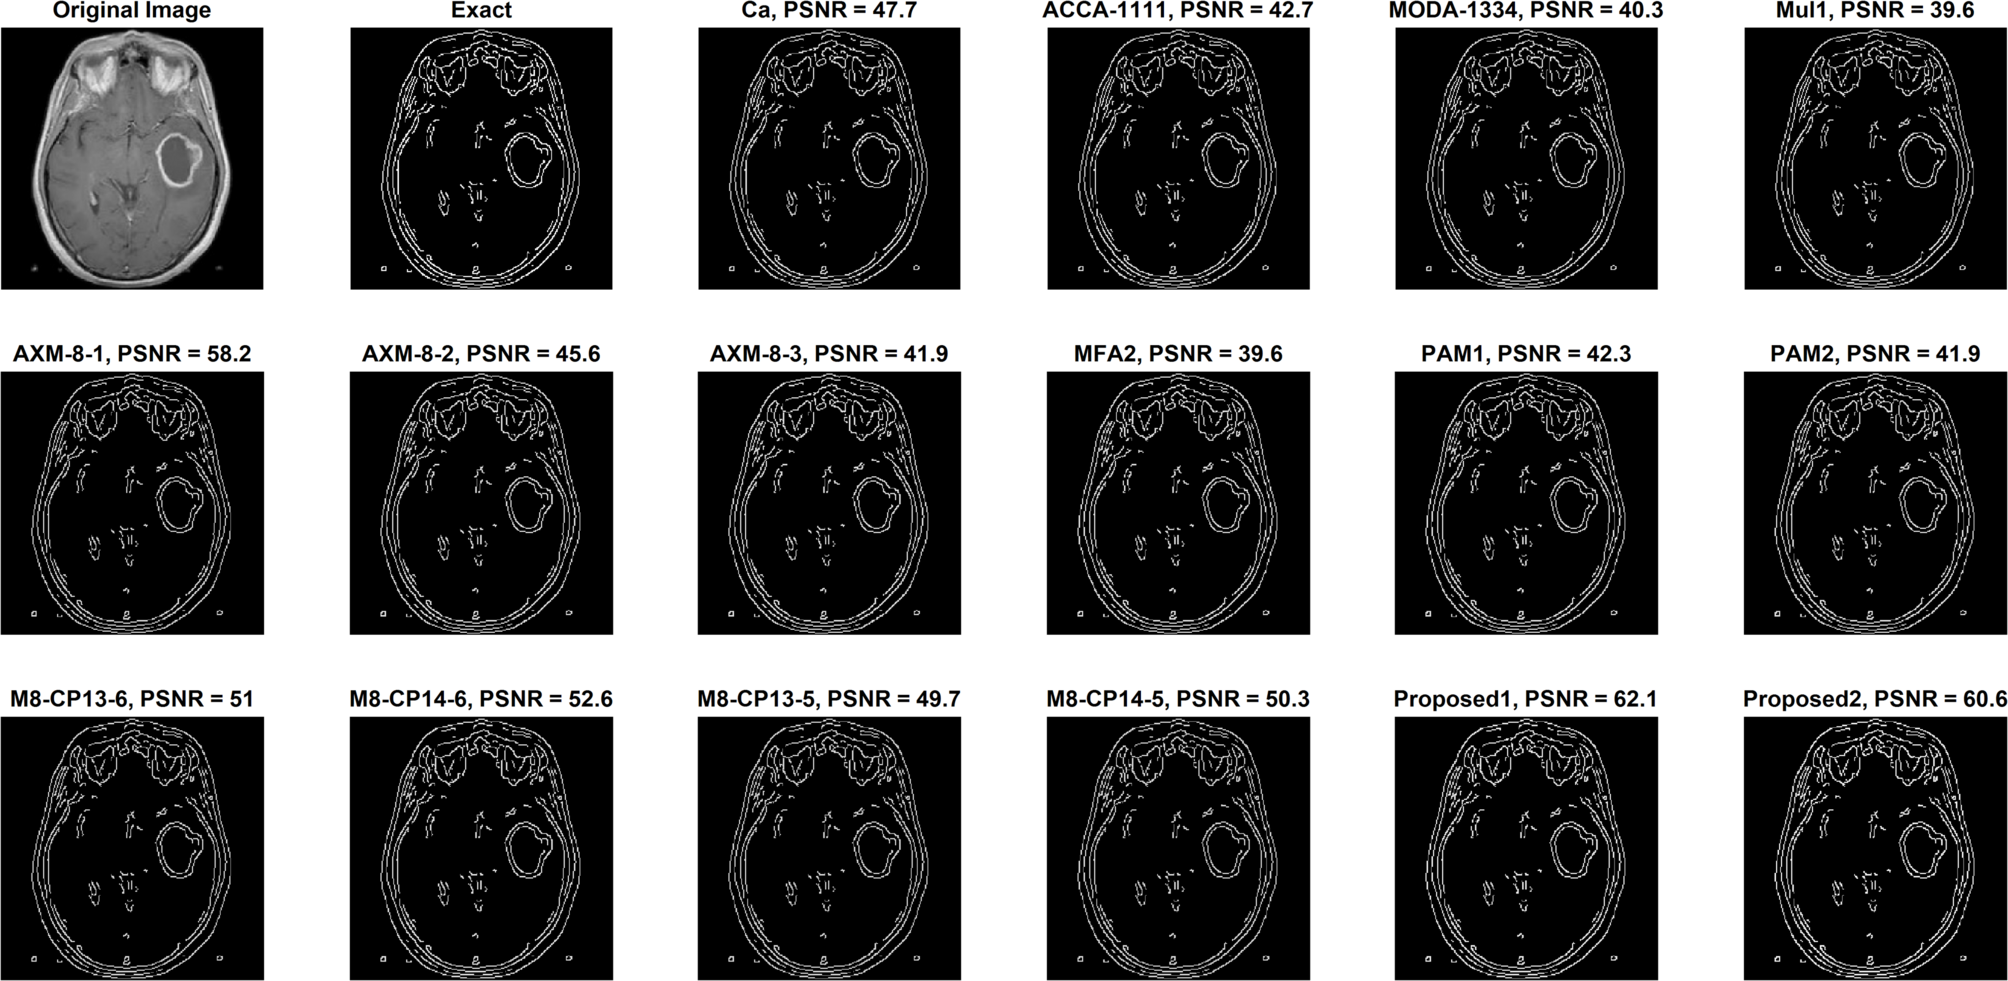

Fig. 17 | Scientific Reports